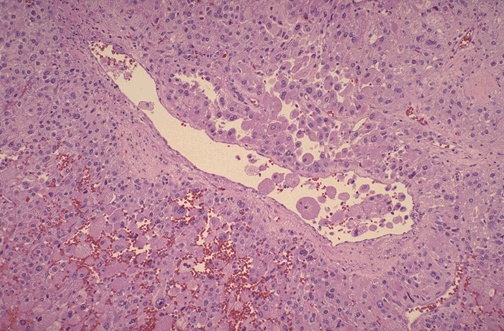

| This high power microscopic appearance of an adrenal cortical carcinoma demonstrates that the neoplasm closely resembles normal adrenal cortex. It is difficult to determine malignancy in endocrine neoplasms based upon cytology alone. Thus, invasion (as seen here in a vein) and metastases are the most reliable indicators. Luckily, most endocrine neoplasms are benign adenomas. |